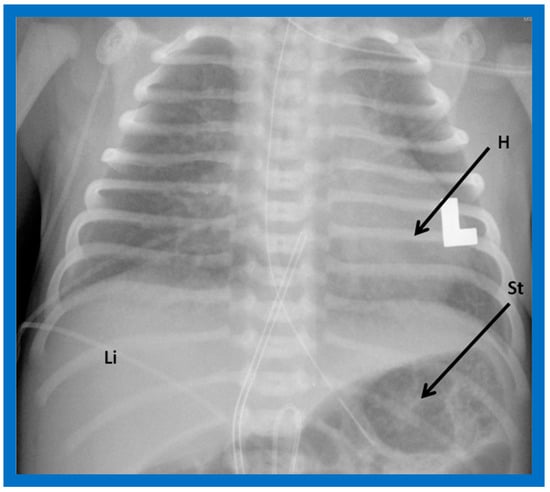

The heart is normally positioned in the left chest (Figure 1) and is designated levocardia.

Figure 1. Chest roentgenogram of a baby demonstrating the heart (H) in the left chest (L), i.e., levocardia. This is the usual position of the heart in most patients. The roentgenogram further demonstrates the liver (Li) on the right side of the abdomen and the gaseous opacity of the stomach (St) on the left side, again normal. This is described as situs solitus of the viscera. L indicates left. Reproduced from reference [4].